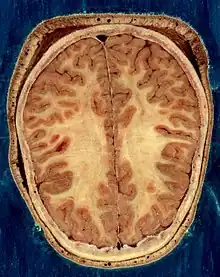

The vertebrate nervous system can also be divided into areas called gray matter and white matter.[19] Gray matter (which is only gray in preserved tissue, and is better described as pink or light brown in living tissue) contains a high proportion of cell bodies of neurons. White matter is composed mainly of myelinated axons, and takes its color from the myelin. White matter includes all of the nerves, and much of the interior of the brain and spinal cord. Gray matter is found in clusters of neurons in the brain and spinal cord, and in cortical layers that line their surfaces. There is an anatomical convention that a cluster of neurons in the brain or spinal cord is called a nucleus, whereas a cluster of neurons in the periphery is called a ganglion.[20] There are, however, a few exceptions to this rule, notably including the part of the forebrain called the basal ganglia.[21]